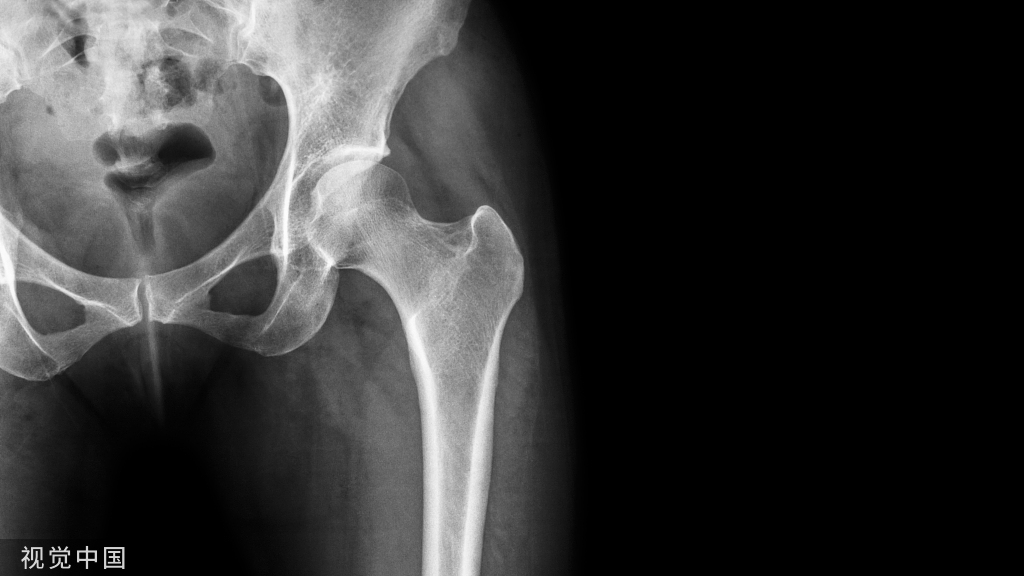

踝关节骨性关节炎合并距下关节炎,术前正侧位 X 线片可见胫距关节及距下关节破坏严重,距骨部分塌陷,关节周围可见骨赘形成。